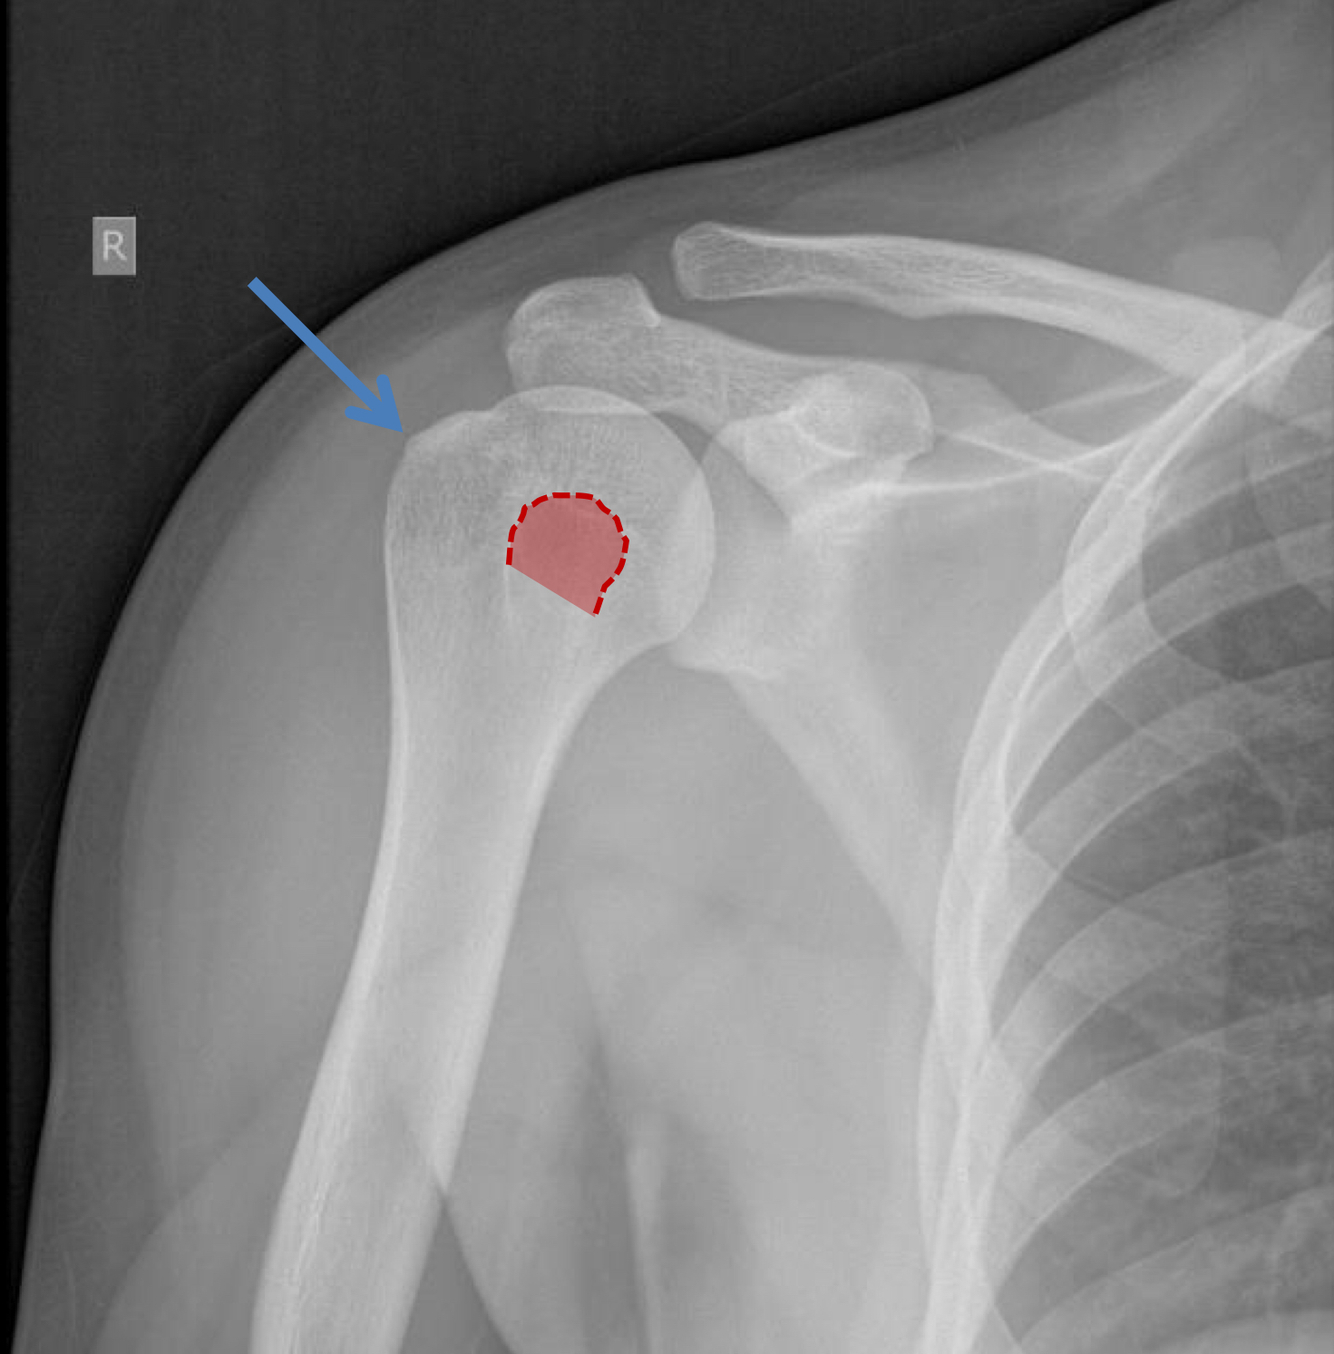

What view is this?

AP shoulder with external rotation

What is the Blue arrow point to?

greater tuberosity of the humerus (which will be more lateral in external rotation)

What is the red area outlining?

lesser tuberosity of the humerus (will be superimposed on metaphysis with external rotation)